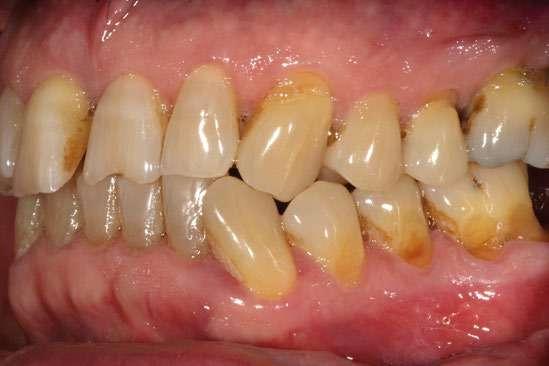

Figura 25-27. Posición inicial en el ClinCheck.

28-30

Figura 28-30. Posición final en el ClinCheck.

A través de la planificación digital en el ClinCheck® Software, se determinaron los movimientos ortodóncicos indicados, que incluyeron: aumento del resalte, corrección del apiñamiento inferior y una combinación de intrusión y extrusión con el objetivo de nivelar márgenes gingivales. Todos estos mo-

vimientos fueron diseñados considerando la fase restauradora posterior. El resultado de la planificación digital de los movimientos ortodóncicos obtuvimos: 19 alineadores en total, 7 superiores y 19 inferiores, los cuales se indicaron cambios cada 7 días como recomienda la casa comercial y se le explicó al paciente la importancia de utilizar los alineadores entre 20 a 22 horas al día. En dicha planificación también se aplicaron ataches estratégicos y se realizaron desgastes interproximales (IPR 0,2–0,3 mm). Se realizaron controles periódicos cada 4 alineadores, en los cuales observamos mejoras progresivas del apiñamiento inferior y la generación controlada de diastemas superiores tal como los planificamos en el software.